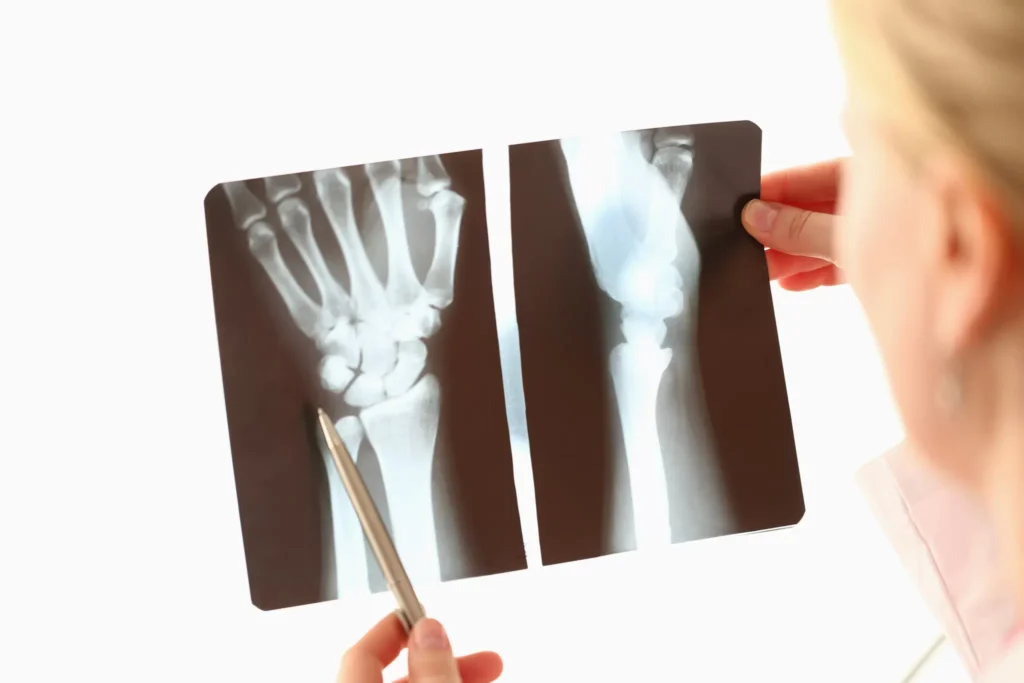

Arm and finger injuries can vary in severity, from minor sprains to complex fractures and nerve damage. Some of the most common types of injuries include

Arm fractures, including breaks in the humerus, radius, ulna, or wrist bones, are common, often resulting from falls, car accidents, or sports injuries. Finger fractures can also occur, affecting the ability to grip or perform fine motor tasks.